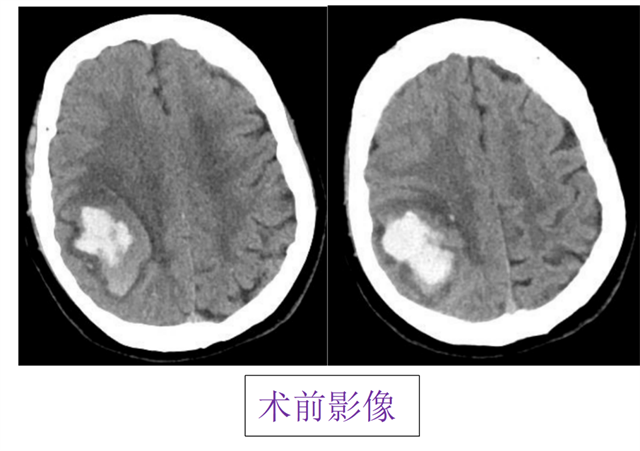

我院神经外科

在河南省援疆专家吴中华主任的带领帮助下

成功完成区域首例

微型机器人精准定位导航下

立体定向颅内血肿穿刺清除引流术

近日